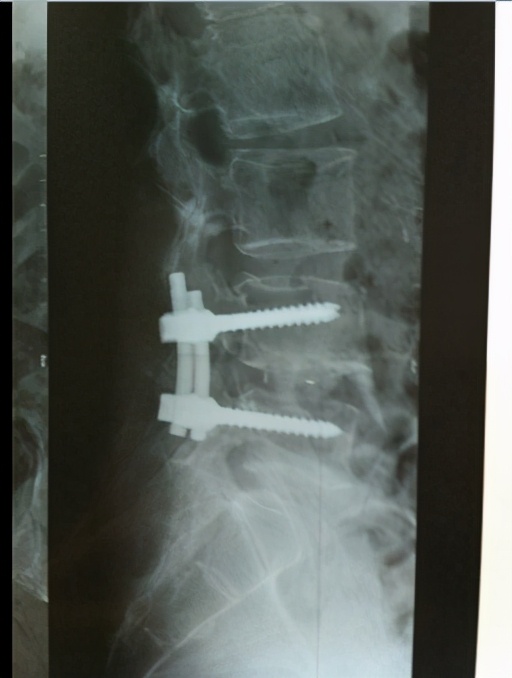

腰椎后方的两个小关节和前方的椎间关节构成三关节复合体,腰椎间盘摘除术后,必然导致椎间盘高度变小,椎间隙变窄,从而导致腰椎三关节复合体的前部结构应力下降,后部结构应力上升,腰椎周围软组织束缚力失衡,脊柱腰段的生物力学紊乱,而引起腰椎不稳。想要失稳的腰椎再稳定可不是太容易的事情,一是需要椎周软组织的功能代偿,二是需要骨质增生、韧带钙化等骨性稳定因素的形成,紧张痉挛的肌群松下相对容易,松弛的肌群想要紧起来,就不是太容易的了。这种情况的出现,笔者推荐的治疗方法就是针灸加中药内服外用,再加上必要的理疗康复,除此之外,就是需要患者的自我保护和时间上的等待了。

椎管内硬膜外纤维化瘢痕增生、粘连是腰椎管手术的基本病理变化,谁也无法改变。纤维化瘢痕及粘连等除了可造成神经牵拉,还可以影响神经根的血供,造成神经缺血、缺氧等营养障碍,导致腰腿痛症状再现。此外椎间盘的再突出,或相邻间盘的突出形成或加重,都可以造成新的神经压迫与刺激症状。出现这些情况,行相邻节段的硬膜外神经阻滞,通过药物浸润,或许能够产生一定的治疗效果,再结合其他的保守治疗方法,以观察治疗效果,如果效果不明显,再手术就成了我们不得不考虑的事情了。